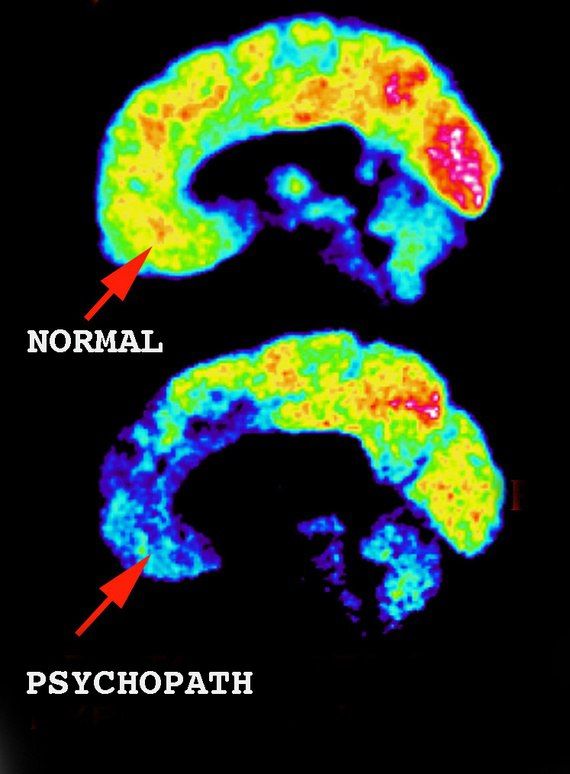

Конечно. Давно уже известно что психопатия это врождённое. Щас найду инфу. В голове нет участка, как почки например второй. Часто в семье допустим 2е детей и один эмпат а другой нарц или психопат в одного из родителей. А воспитывали мама одинаково!!!!! Все очевидно. Я не спорю с теми кто утверждает, что это типо можно в детстве как то там скорректировать. Это их теория, но я уверена что врождённое.